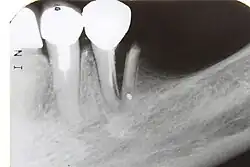

Reabsorção de raiz

A reabsorção radicular após lesões dentais traumáticas, seja localizada ao longo da superfície radicular ou dentro do canal radicular, parece ser uma sequela de eventos de cicatrização de feridas, onde uma quantidade significativa do ligamento periodontal (LPD) ou polpa foi perdida devido as consequências do trauma agudo. [54]